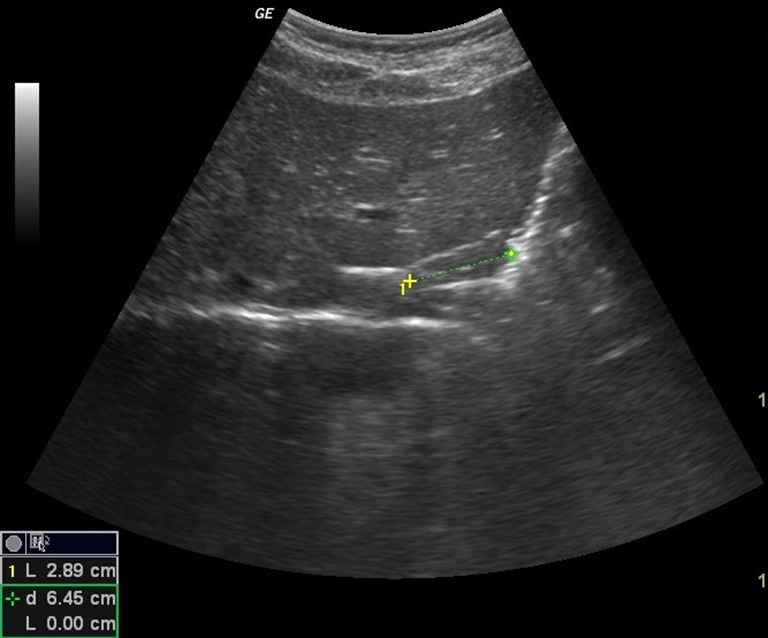

- Comprimento do esôfago abdominal;

- Espessura da parede esofágica;

- Diâmetro do esôfago;

Entre os principais achados descritos estão medidas do esôfago abdominal, do ângulo de His, da parede esofágica e da dinâmica do esvaziamento e da acomodação gástrica, embora os valores de referência ainda não sejam bem padronizados.

- Mensuração da espessura da parede esofágica.

- Comprimento do esôfago abdominal.

A ultrassonografia permite a avaliação do esôfago distal por meio da mensuração do diâmetro esofágico, da espessura da parede e do comprimento do segmento abdominal. O estômago é analisado predominantemente sob o aspecto funcional, com destaque para o estudo do esvaziamento gástrico, calculado a partir da área antral, e da acomodação do estômago proximal.